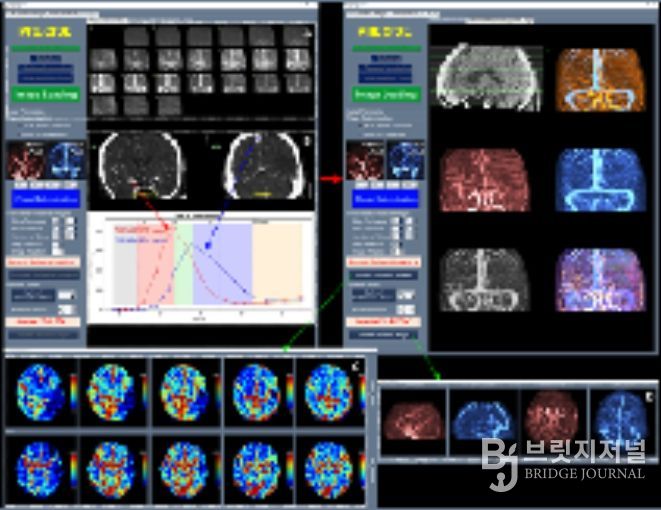

이와 함께 허혈성 뇌혈관 질환 환자를 대상으로 혈관재개통 치료가 필요한 환자 선별을 지원하는 소프트웨어 등 다양한 진단·치료 보조 AI 의료기기들이 혁신의료기기로 지정됐다.